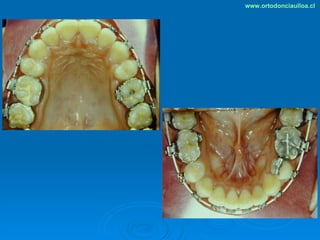

Este documento presenta dos casos clínicos de pacientes que recibieron tratamiento de ortodoncia. El primer caso fue de una paciente femenina de 14 años con apiñamiento dental y mordida cruzada que fue tratada mediante extracción de premolares y alineamiento dental. El segundo caso fue de un paciente masculino de 14 años con clase II esqueletal y desarmonía dentomaxilar que fue tratado con extracción de premolares y corrección de mordida. Ambos casos mostraron mejoría después de 3 años de tratamiento.